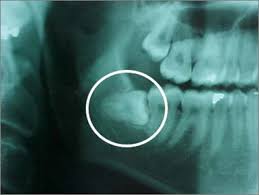

Hasilnya gigi Diya mengalami proses penskaleran or also we call as scaling. Pengalaman pertama kali scaling gigi ni memang sangat awkward. Agak terkejut jugak lah bila doktor terus buat experiment dekat gigi Diya. Rasa macam ish dah kenapa tiba2 gigi Diya ada mesin bagai. Wuuu..sangat ngilu masa doktor pergi korek-korek benda asing dekat gigi tu, Gusi-gusi diratah dengan rakus..kui3. Baru-baru ni adik dengan abang Diya ada ke klinik gigi untuk tampal gigi. Dengar diorang cerita doktor tu pergi gerudi lubang tu sebelum letak kapur nak tutup lubang dekat gigi rosak tu pun dah buat diya seram. Bila rasai sendiri pengalaman diorang baru Diya paham. Sangat ngilu. Lepas doktor selesai buang semua daki2 dekat celah gigi tu dia suruh kumur-kumur. Darah kau, kemain banyak lagi, terkejut.....kih3.....dah lama tak jumpa doktor gigi lah katakan.. Sebelum tu doktor ada korek gusi dekat celah wisdom tooth atau orang panggil gigi bongsu. Gigi akhir tumbuh. Dan lagi sekali diya dikejutkan gigi bongsu Diya rupa dia cenggini di bahagian kiri bawah:

Elok je dia tidur macam tu, (ehsan dari google lagi)